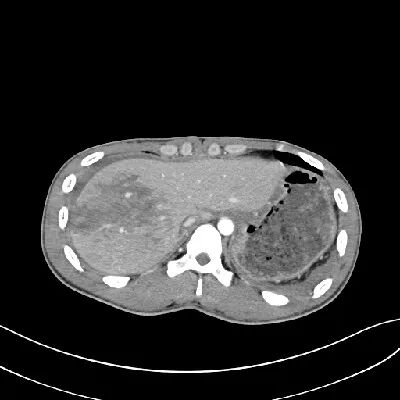

CT表现:

对于肝损伤CT能确定其存在及范围,且有非常高的特异性。肝包膜下血肿会形成新月形或半月形的低密度或等密度区,相应的肝实质会受压变平而显示肝表面的边界失去正常的弧形而变平,尤其血肿新鲜时其CT值与肝实质类似,此时注意肝表面周缘的改变亦就显得重要。

一般来讲,血肿的CT值随时间的推移而减低。在肝实质的血肿则常常显示圆形、卵圆形或星状低密度影。肝撕裂会见到单一或多发的线样低密度,边缘模糊。